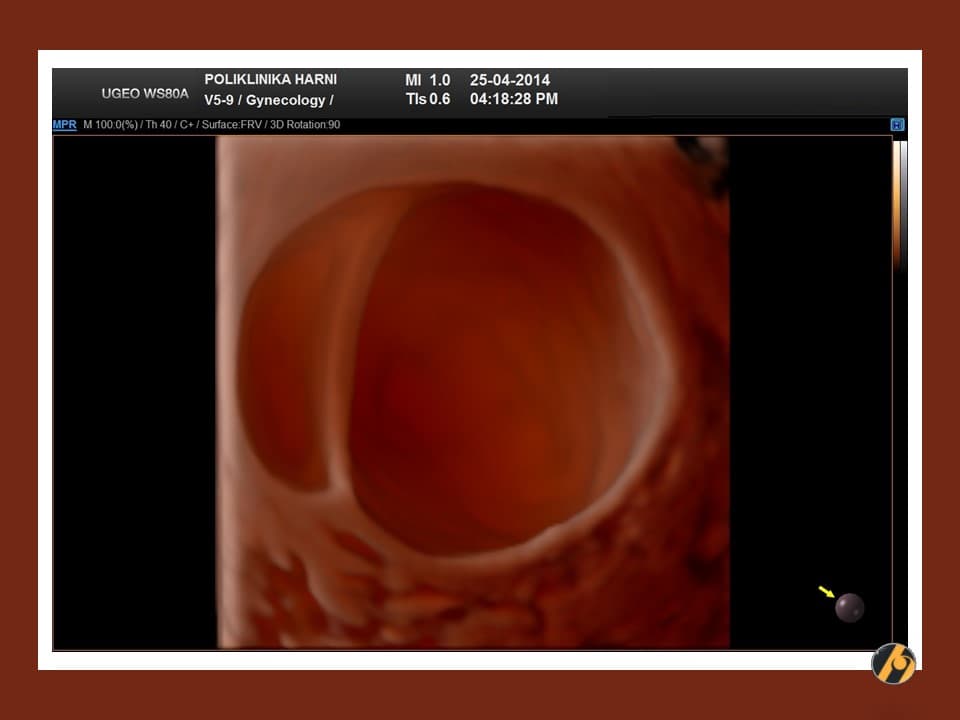

- Unilokularna cista: cista s jednom šupljinom bez septi i solidnog tkiva.

- Unilokularna solidna cista: unilokularna cista s jednom šupljinom i solidnom komponentnom. Solidna komponentna može biti papilarna projekcija ili bilo koji drugi tip solidnog tkiva.

Unilokularna cista ne može imati niti jedan solidni dio. Multilokularna cista ne može imati niti jedan solidni dio. Ako postoji solidni dio, riječ „solidan“ mora biti u opisu tumora. Na primjer: umjesto da se napiše cista s jednom solidnom komponentnom, piše se unilokularna solidna cista.